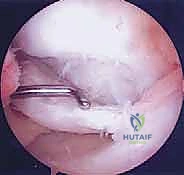

4. التنظير المفصلي التشخيصي (Diagnostic Arthroscopy)

في بعض الحالات المعقدة، قد يكون التشخيص النهائي وتقييم قابلية الشفاء (عن طريق لمس الغضروف بأداة جراحية لتقييم صلابته) لا يتم إلا من خلال المنظار الجراحي. يستخدم الدكتور هطيف كاميرات 4K عالية الدقة لرؤية المفصل من الداخل بوضوح لا مثيل له.

1. تقنية التثقيب أو الكسور الدقيقة (Microfracture / Drilling)

- الهدف: تحفيز نخاع العظم لإنتاج غضروف بديل.

- كيفية الإجراء: باستخدام المنظار، يقوم الدكتور هطيف بتنظيف المنطقة التالفة من الغضروف، ثم يستخدم أداة دقيقة لإحداث ثقوب صغيرة في العظم تحت الغضروفي المكشوف. هذه الثقوب تسمح بخروج الدم والخلايا الجذعية من نخاع العظم لتشكيل جلطة دموية (Super Clot) فوق المنطقة المصابة. بمرور الوقت، تتحول هذه الجلطة إلى نسيج ندبي يسمى "الغضروف الليفي" (Fibrocartilage).

- الاستطبابات: الآفات الصغيرة (أقل من 2-3 سم مربع)، والآفات المستقرة التي تحتاج إلى تحفيز التروية الدموية.

- الميزة: إجراء بسيط بالمنظار، فترة نقاهة أولية سريعة.